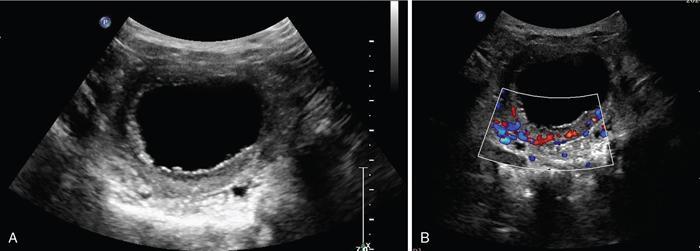

Anmol Bhatia, Ajay Prashanth Dsouza, Kushaljit Singh Sodhi Urinary tract infection (UTI) is a common cause of febrile illness in children, second only to respiratory tract infections. The incidence before 14 years of age ranges from 3%–10% in girls and 1%–3% in boys; however, the incidence is more in boys during infancy. The clinical spectrum in increasing order of severity ranges from asymptomatic bacteriuria and cystitis to acute pyelonephritis and septicemia. Urinary tract anomalies, prematurity, indwelling urinary catheters, lack of circumcision in boys and high-grade vesicoureteral reflux (VUR) are some of the common predisposing factors. Although the clinical outcome is good in most patients, a few may develop long-term complications like hypertension, chronic renal insufficiency and end-stage renal disease. Given the poor localizing signs and the dreaded complications, a high degree of clinical suspicion, prompt diagnosis and treatment and tailored follow-up play pivotal role in management of these patients. Urine culture is the most important tool to establish the diagnosis and identify the causal pathogen, Escherichia coli being the most commonly isolated bacteria. Midstream clean catch urine sample is used in toilet-trained children while the sample is often obtained by suprapubic aspiration or transurethral catheterization in younger age group. A colony count of >105 CFU/mL of a single species in a midstream clean catch sample is confirmatory. Although imaging can aid in the diagnosis of an ongoing UTI, the main role lies in identifying the associated urinary tract abnormalities and also to look for the extent of consequent renal insult. Some of the common anatomic abnormalities predisposing to recurrent and complicated infections include VUR, congenital pelviureteric junction (PUJ) obstruction, ureterocoele, posterior urethral valve, ureteral duplication and neurogenic bladder. The imaging modalities commonly used in children are ultrasound (US), which helps in detection of structural anomalies, hydroureteronephrosis, urinary tract stones and renal scars; voiding cystouretherography (VCUG) for detecting VUR and 99mTc-labelled dimercaptosuccinic acid (DMSA) scans to look for renal scars. US is often used as the first-line imaging modality because of its easy availability, low cost, non-invasiveness and lack of ionizing radiation. UTI, when confined to the lower genitourinary tract, frequently called as cystitis, reveals diffuse bladder wall thickening (Fig. 10.8.1A) with hazy margins on grey-scale US, which may show increased vascularity on Doppler (Fig. 10.8.1B). Floating echoes in the urine are commonly seen. The distal ureter may also be dilated and show mural thickening. Since UTI confined to bladder is mostly uncomplicated, it does not usually warrant a further imaging workup. However, in cases of severe bladder trabeculations, unilateral gaping ureteral ostium, open bladder neck, follow-up for bladder outlet obstruction, dysfunction or VUR may be indicated after the acute infection settles. Inflammatory response to the infection leads to swelling and decreased perfusion in renal parenchyma. Findings on intravenous urography (IVU) include renal enlargement, a diffuse or patchy striated nephrogram with delayed opacification and effacement of pelvicalyceal system. On renal US, diffuse or localized renal enlargement may be the only finding. Other typical findings include altered parenchymal echotexture, usually hypoechoic (Fig. 10.8.2) but may be hyperechoic, along with poor corticomedullary differentiation. Colour or power Doppler study reveals reduced vascularity. On 99mTc DMSA or glucoheptonate scans, photopenic defects due to reduced accumulation of renal cortical tracers are seen. The defects may be solitary, multiple or may involve the entire kidney giving a mottled appearance. DMSA renal scintigraphy with a sensitivity of 99.9% is the imaging modailty of choice for diagnosing acute pyelonephritis (APN). Among the patients with UTI, 50%–91% show defects on nuclear scans, suggestive of acute pyelonephritis. When both VUR and APN are present, scintigraphy is abnormal in 79%–86% of children. Permanent scars are known to occur in 38%–57% of children diagnosed with APN on nuclear scan, not withstanding the grade of VUR. 99mTc DMSA scan is the imaging modality of choice for detection of renal scars and they also appear as photopenic defects; however, the temporal course of study helps to differentiate it from APN. Thus, follow-up scanning at 3–6 months may be suggested to detect if the kidney has healed or scarred. CECT reveals striated nephrogram along with multiple wedge-shaped or round hypoenhancing areas with apices directed towards calyces (Fig. 10.8.3). Perinephric fat stranding may also be seen. MRI reveals wedge-shaped or round, T2 hyperintense lesions with decreased signal on inversion recovery sequences. And similar to CECT, striated nephrogram and inflammatory changes in perinephric fat may be demonstrated. MRI can also help in detection of renal scars. Despite it being a radiation-free modality with utility in poor renal function, MRI is less often used due to limited availability, higher cost, longer scan times and need for prolonged sedation. Acute focal bacterial nephritis is a localized or segmental form of acute pyelonephritis, also known as acute lobar nephronia, usually affecting only a renal pole or one moiety in a duplex kidney. It appears as an ill-defined, poorly marginated mass in contrast to renal abscess which is relatively well-defined, surrounded by enhancing walls (Fig. 10.8.4). The mass is usually hypoechoic on USG with low-level internal echoes and shows reduced vascularity on Doppler. CECT shows ill-defined or wedge-shaped hypodense areas which correspond to focal photopenic defects on nuclear scans.